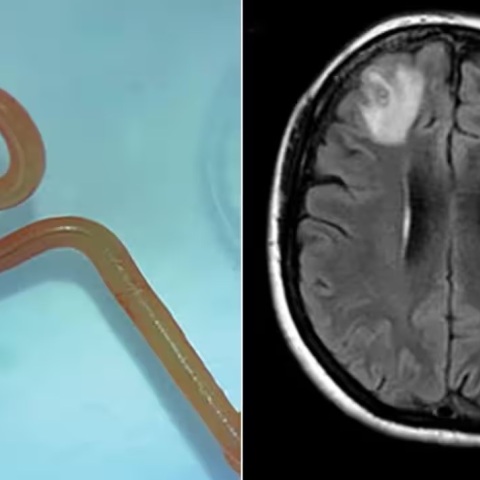

Μοναδική περίπτωση στα παγκόσμια χρονικά - Πώς εντοπίστηκε από τους γιατρούς